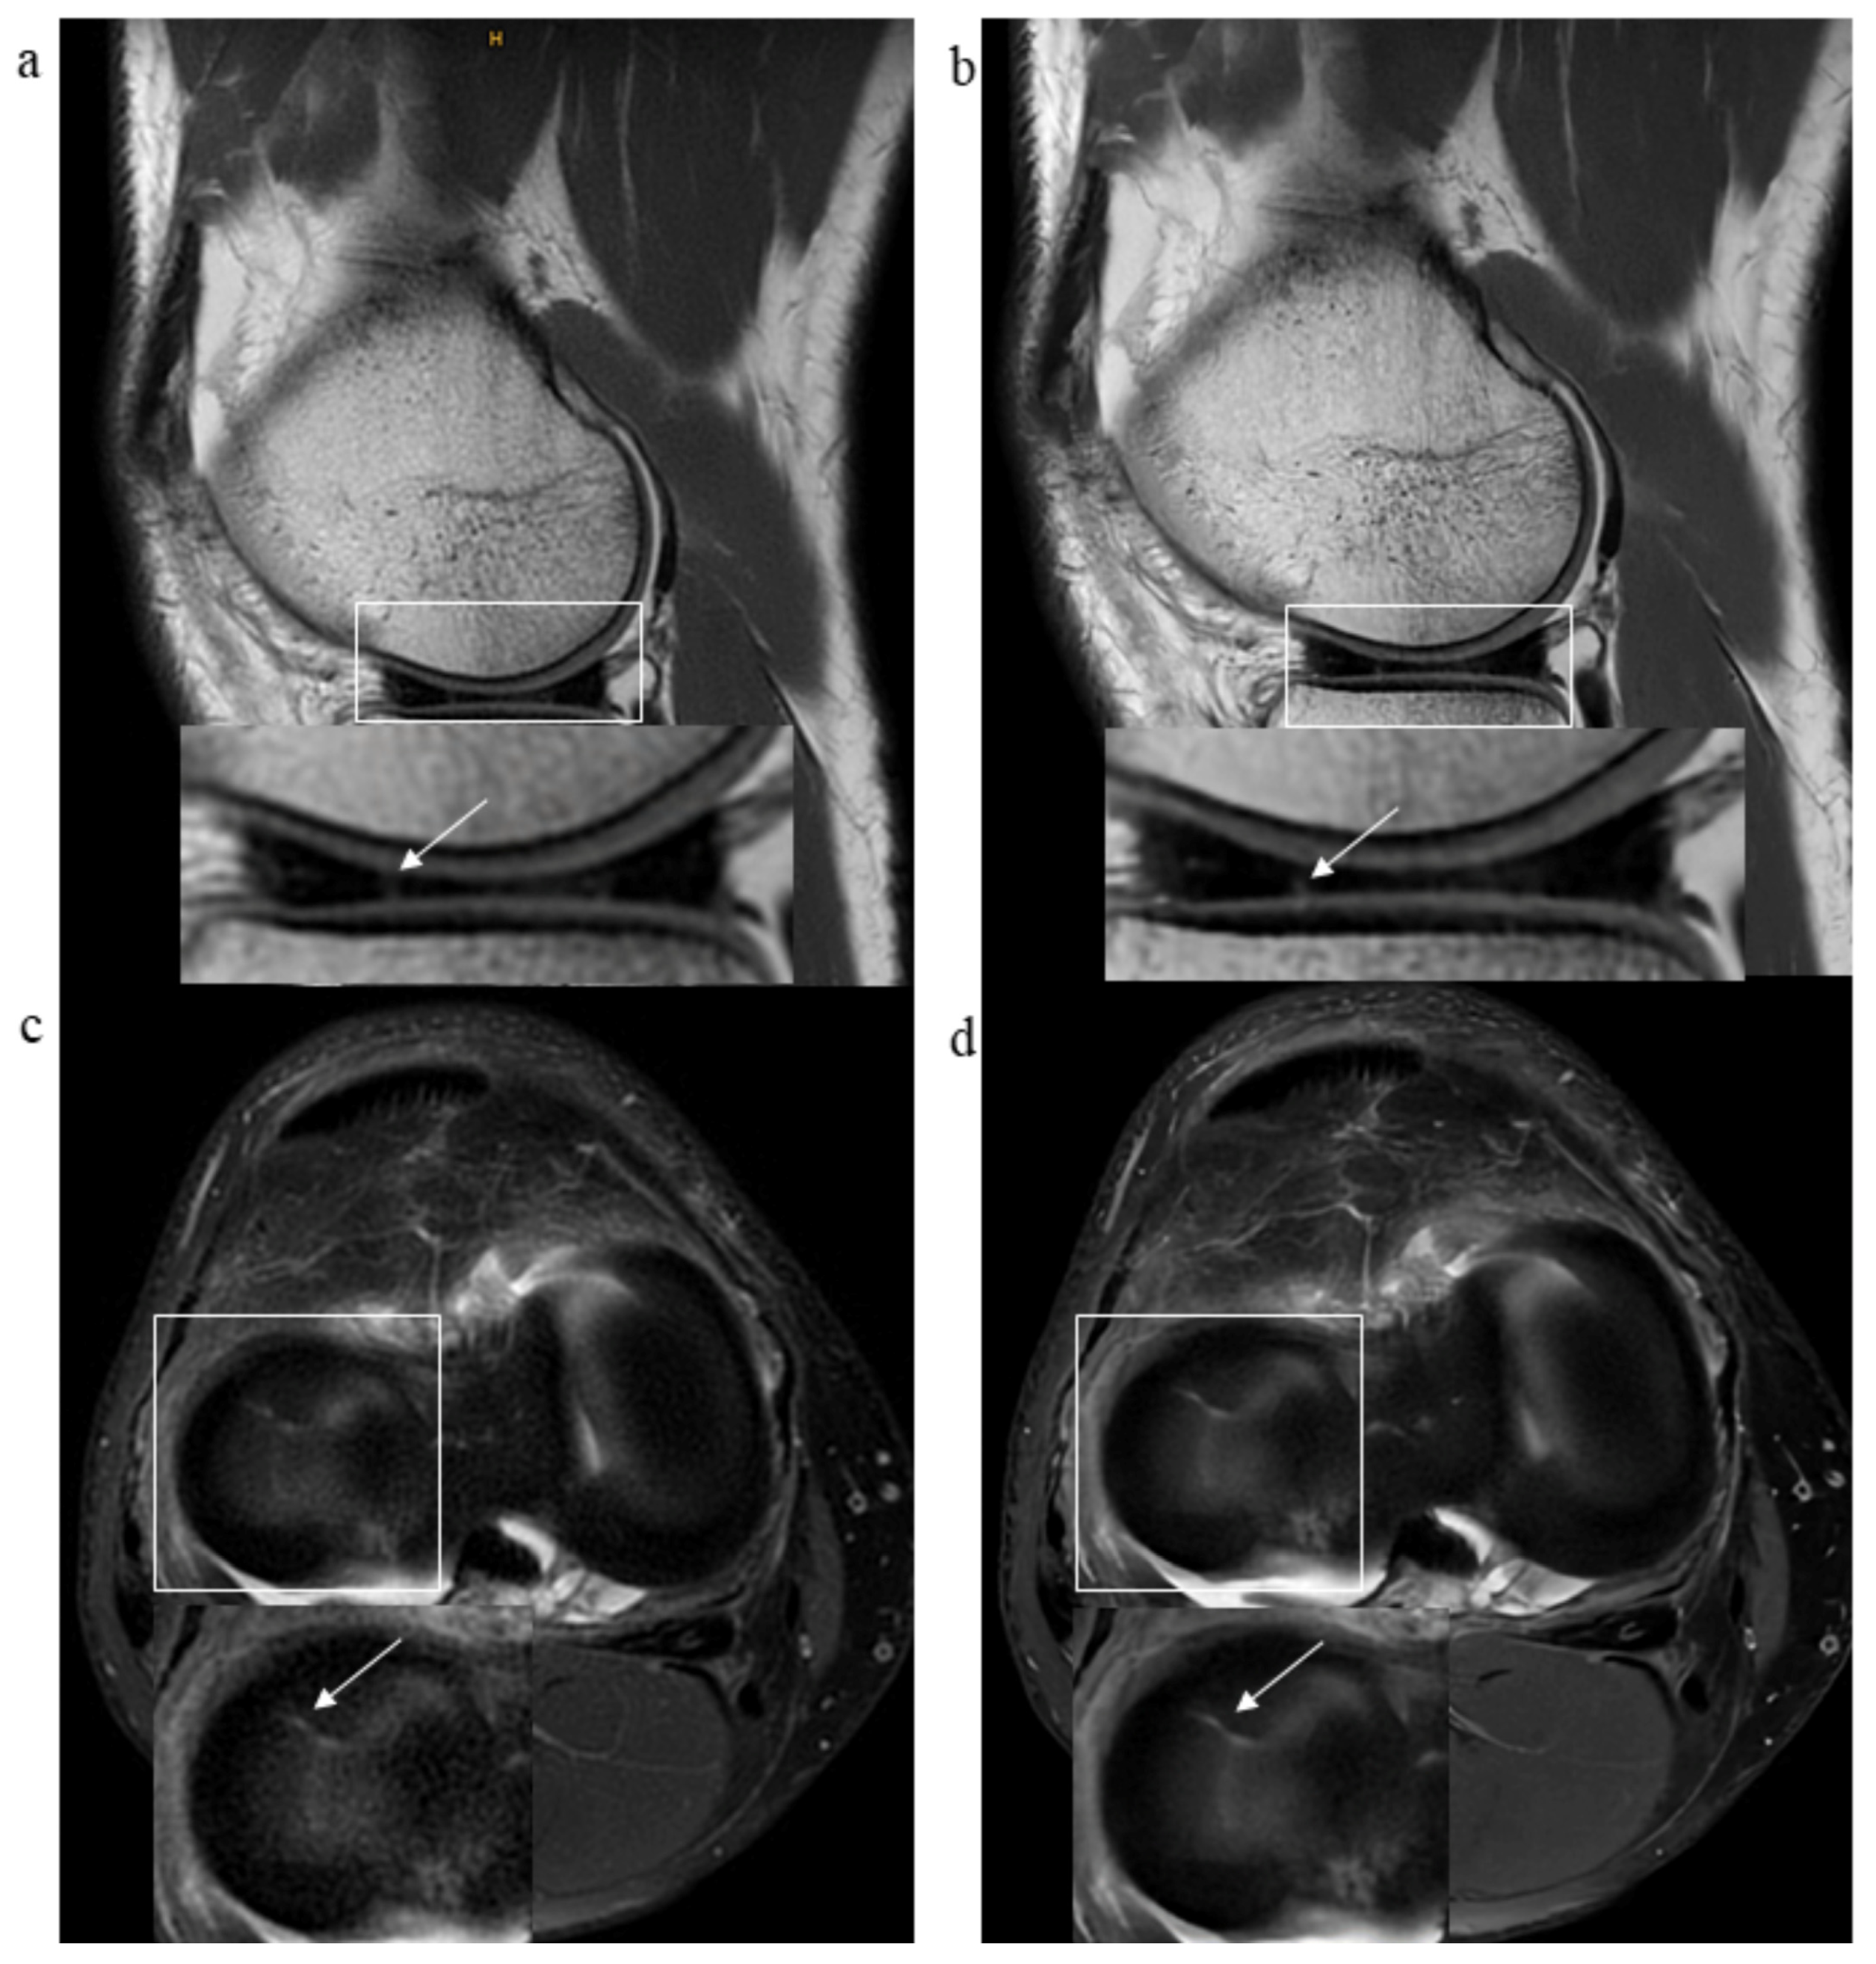

3.2. Pathological Findings